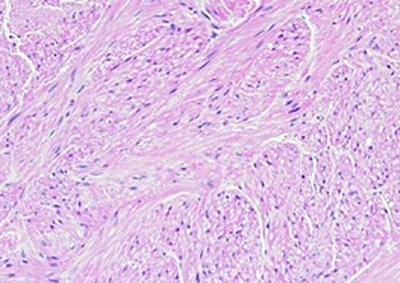

Histology showed multiple dermal nodules; some originated from the arrector pili muscles, composed of interlacing smooth muscle bundles, with bland, blunt-ended spindle cell nuclei and abundant fibrillary eosinophilic cytoplasm.

Cutaneous leiomyoma originating from an arrector pili muscles (200x)

Smooth muscle bundles, with bland, blunt ended spindle cell nuclei (400x)